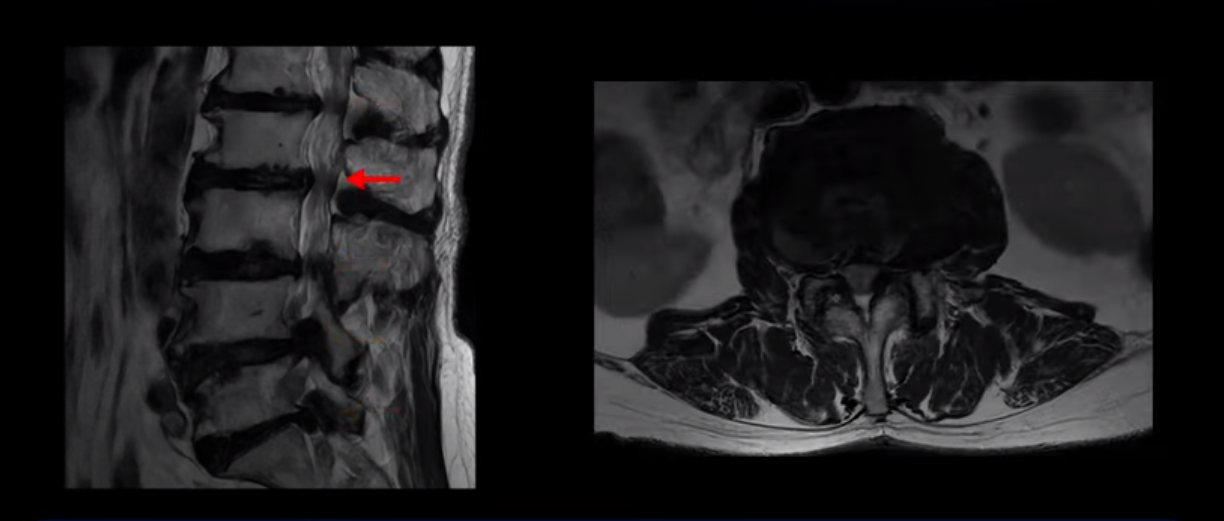

이 환자분은 MRI로 보면 허리 여러 마디가 신경이 매우 심하게 눌려 보이는 분입니다. 이분 MRI를 보면서 간단히 설명해 드린 후 어떻게 이렇게 신경이 심하게 눌린 환자분이 수술 없이 근육신경재활치료로 좋아질 수 있는지, 다리가 아파 걷지 못하는 환자가 어떻게 안 아프고 잘 걸을 수 있게 되는지, 10년 동안 괴로웠던 양 발의 시린 증상은 어떻게 사라질 수 있는지, 치료는 어떻게 하는지 자세히 설명 드리겠습니다.

MRI 보시면 (2-8) 허리의 5마디가 전부 다 심하게 퇴행되어 있습니다.

5마디 전부 다 심한 중심성 협착이 있습니다.

이렇게 모두 다 심하게 막히는 경우는 드문데요. 또한 오른쪽, 왼쪽 신경이 빠져나가는 추간공도 다 심하게 막혀있습니다.

오른쪽, 왼쪽 이렇게 신경 구멍들이 다 좁아지고 신경이 눌리니까 양쪽 다리가 발바닥까지 아파서 걷기 어렵고 양쪽 발이 10년 넘게 시린 겁니다. 당연히 수술해서 눌린 신경을 풀어줘야 한다고 들으셨는데요. 이런 환자분을 어떻게 수술 없이 치료할까요? 지금부터 설명해 드립니다.

이분 신경이 눌리는 증상은 오래됐지만, 증상이 아주 심해진 건 올해 들어와서입니다. 그럼, 이분 MRI 영상도 이렇게 심하게 안 좋아진 게 올해 들어와서일까요? 이분의 MRI로 보이는 협착은 아주 오래된 겁니다. 그래서 신경 구멍이 심하게 좁아진 것도 올해가 아니고 오래된 겁니다. 작년, 재작년에 훨씬 덜 아팠을 때 MRI를 찍었어도 신경 구멍 좁은 정도는 별반 차이가 없었을 겁니다.

실제로 수많은 논문에서 70세 이후 MRI로 협착이 보여도 아프지 않은 무증상 협착이 많다고 설명합니다. 협착이 있어도 안 아픈 사람들이 많다는데, 이게 왜 그럴까요? 근육 기능이 정상적이고 좋은 사람들은 근육이 허리를 잘 지지해 주니까 협착이 있어도 신경이 덜 눌리거나 안 눌리는 겁니다. 즉 근육이 좋으면 신경이 덜 눌리고 근육이 좋아지면 협착증이 좋아지는 겁니다. 그래서 저희가 근육 재활치료를 통해 근육의 기능을 회복시키면서 동시에 신경의 기능을 회복시키는 치료를 하는 겁니다. 이런 분들이 근육 재활치료를 통해서 협착증 증상이 좋아진다면 이런 분들의 협착증도 아프지 않은 무증상 협착으로 바뀌게 되는 겁니다.